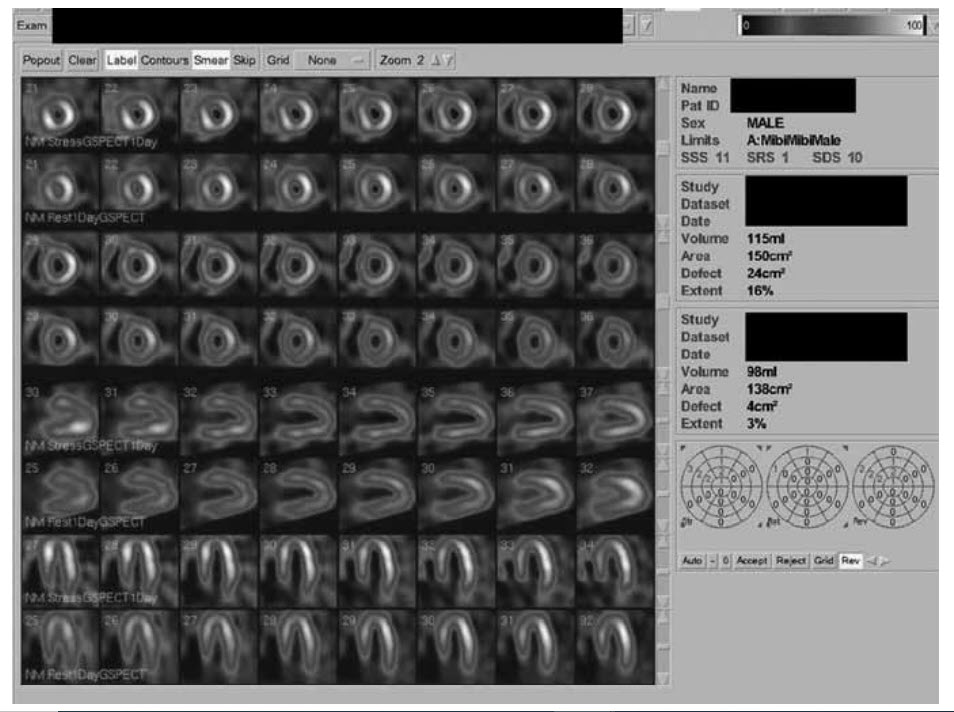

What would you do based on your interpretation of the MPS study shown in Figure below?

A. Revascularization to LAD

B. Revascularization to RCA

C. DSE

D. Medical therapy

E. CTCA